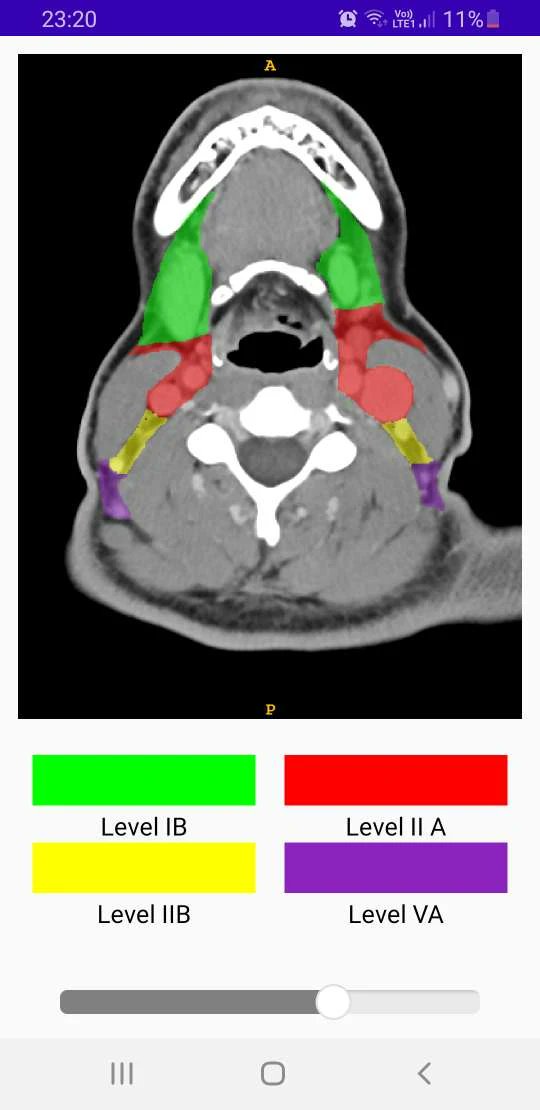

Ct Neck Levels Radiology. learn the radiological anatomy of the head and neck on a ct scan in axial, coronal, sagittal and 3d sections. national diagnostic reference levels (drls) and achievable doses (ads) as a function of patient size are provided for the 10 most common adult ct. in the emergency setting, a systematic approach to interpreting neck ct findings, including. The case is for teaching purposes and shows the anatomy of the neck. learn how the lymph nodes in the neck are divided into six anatomic levels for head and neck cancer staging and therapy planning. a case study of contrast ct of the neck with labeled and unlabelled images. Find the anatomical parts, lymph node levels,. learn how to identify the cervical lymph node levels of the head and neck on ct images, according to the consensus guidelines of international experts. a comprehensive guide to the anatomy and function of the cervical lymph nodes, divided into 10 levels based on the american head and neck society. the materials presented in this website illustrates the consensus reached among cooperatives groups with respect to the.

a case study of contrast ct of the neck with labeled and unlabelled images. the materials presented in this website illustrates the consensus reached among cooperatives groups with respect to the. learn how to identify the cervical lymph node levels of the head and neck on ct images, according to the consensus guidelines of international experts. a comprehensive guide to the anatomy and function of the cervical lymph nodes, divided into 10 levels based on the american head and neck society. The case is for teaching purposes and shows the anatomy of the neck. in the emergency setting, a systematic approach to interpreting neck ct findings, including. national diagnostic reference levels (drls) and achievable doses (ads) as a function of patient size are provided for the 10 most common adult ct. learn how the lymph nodes in the neck are divided into six anatomic levels for head and neck cancer staging and therapy planning. Find the anatomical parts, lymph node levels,. learn the radiological anatomy of the head and neck on a ct scan in axial, coronal, sagittal and 3d sections.